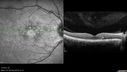

45 year old man was told to come in because of ‘white spots on their retina’. He now has to take his glasses off to read labels. He has always had trouble with oncoming headlights messing up his vision for a short time. VA OD: cc20/20 NscJ1 OS: cc20/20 NscJ1+ Pisciform lesions in the macula of both eyes.

Fundus Flavimaculatus - Asymptomatic - Spectral Domain OCT Line Scan740 views45 year old man was told to come in because of ‘white spots on their retina’.